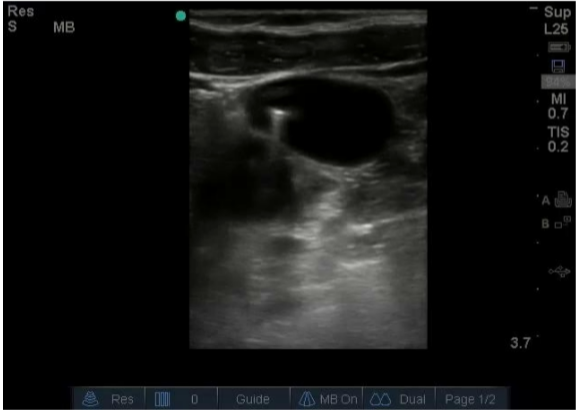

Ultrasound view